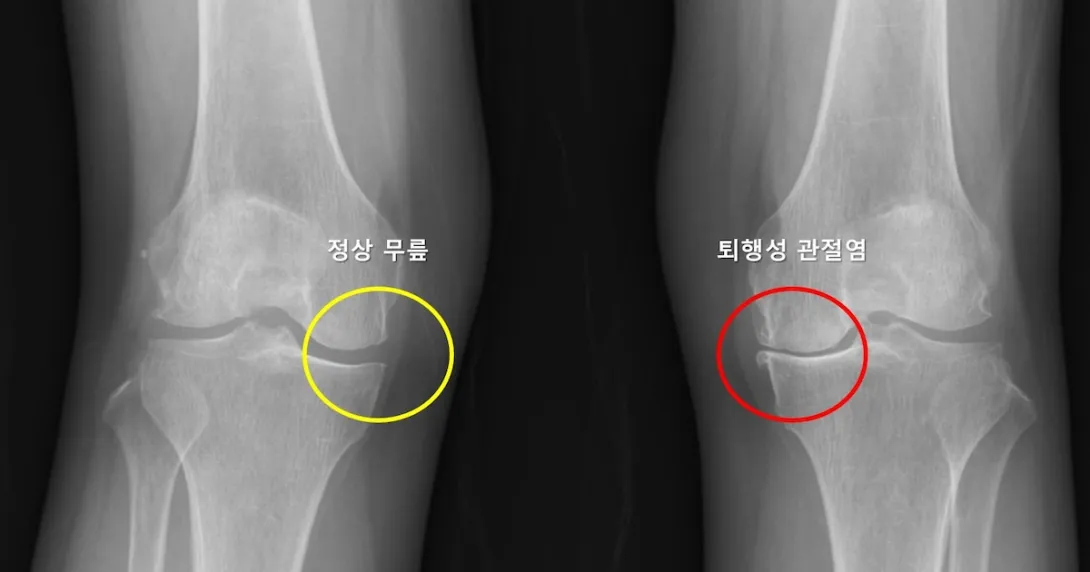

Photo courtesy of Seoul National University Hospital

Researchers from Seoul National University Hospital (SNUH) have developed an AI model for predicting the likelihood that patients with unilateral osteoarthritis would develop the same condition in their other knee.

A major finding of the study, published in Wiley's Journal of Orthopaedic Research, was that a reduction in the lateral joint space of the contralateral knee is a major risk factor for osteoarthritis of the contralateral knee, increasing the risk by 4.5 times.

The study also demonstrated for the first time that the severity of arthritis and the pain and function index of the unilateral knee arthritis are greatly associated with the development of osteoarthritis in the opposite knee.